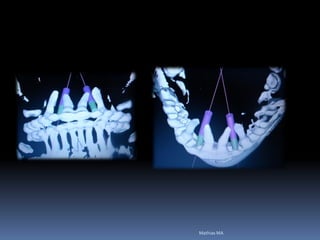

Resoluções em 3-D

Guia Virtual

Prototipagem e Estereolitografia

Guias em 3-D

Futuro ou Presente?

van Steenberghe et al. (2002).

Guia cirúrgico

•Permite o posicionamento ideal da fresagem

através de orifício em guias transparentes

•Utilização de tubos, cones ou somente orifícios

realizados por fresas

•Liberdade controlada da fresa